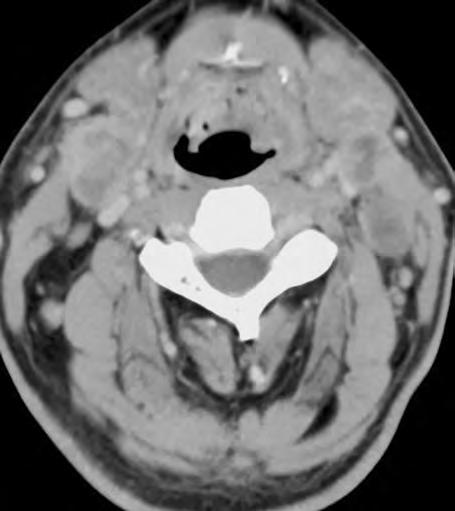

1.2 Glioblastom – ve srovnání s CT poskytuje MR vyšetření více detailů jak o struktuře nádoru, tak i o jeho prostorovém rozsahu, umístění a vztahu k mozkovým strukturám. Za příklad slouží parasagitální řez v T1 váženém čase po aplikaci kontrastní látky i.v.

Obr. 1.3 CT pokročilého astrocytomu III.stupně, který je nápadný rozsahem své velikosti, expanzivním chováním a kolaterálním edémem.